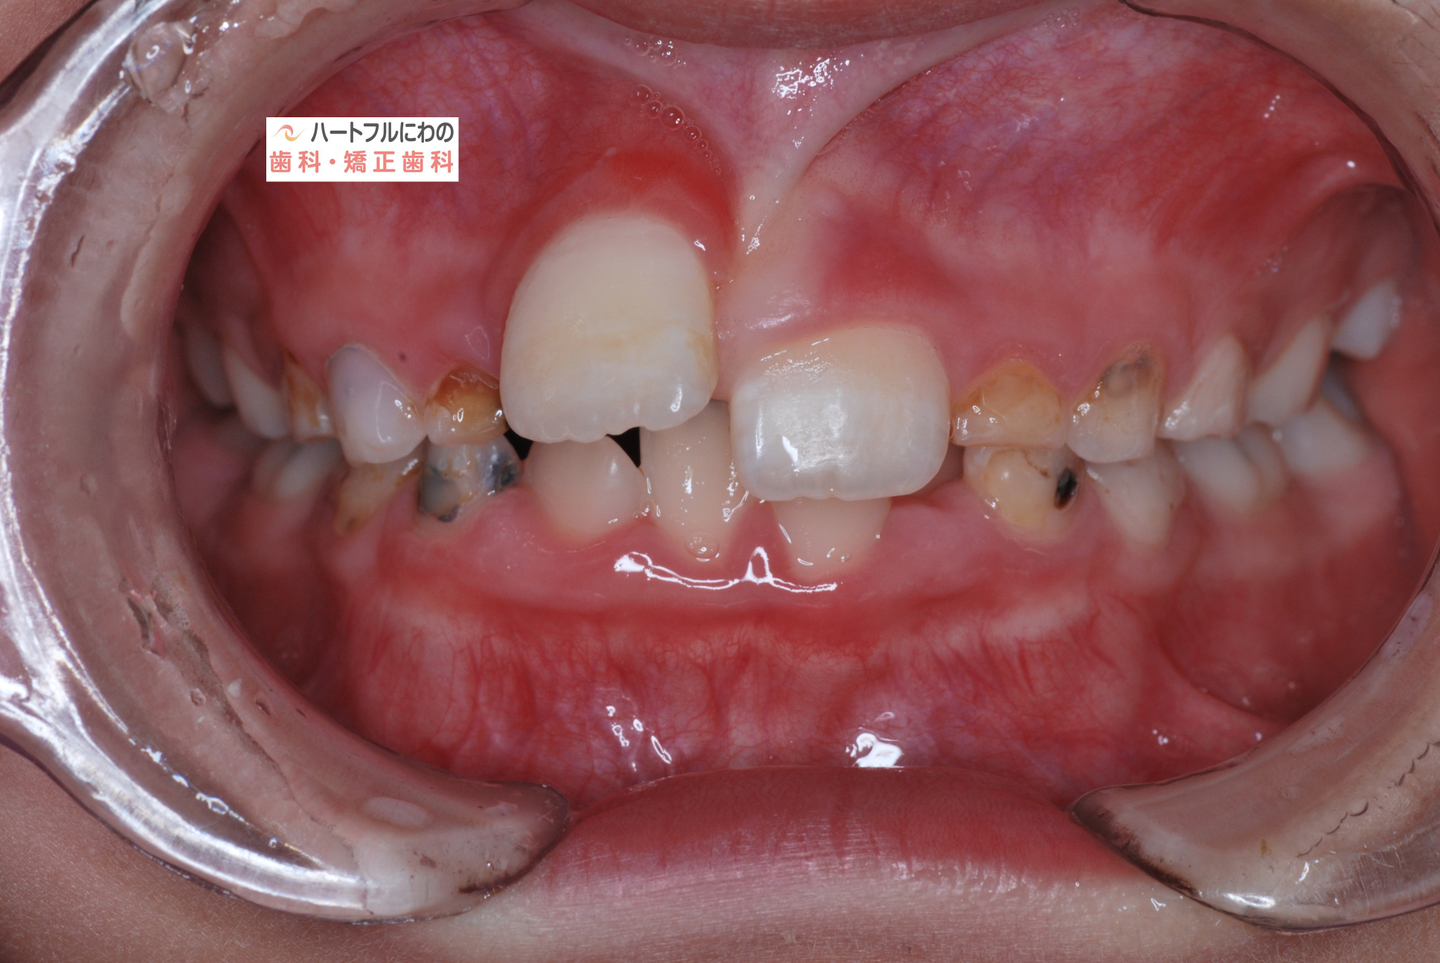

お口の中を拝見すると、上下の叢生(いわゆるガタガタ、乱ぐい)がみられ、多数の虫歯と歯肉炎がみられました。上唇小帯(上唇のすじ)の問題もありました。口呼吸で口腔内が乾燥すると通常の何倍も歯垢が付きやすくなり、虫歯や歯肉炎が頻発します。口呼吸の強い子は重なっている部分のかみ合わせが深い(下の歯がほとんどみえない)のもよく見られる特徴です。

約半年間、成長不全の顎骨を正常に整え、歯の移動も並行して行いました。治療開始から口呼吸の問題は約2か月で大幅に改善、3か月で夜間睡眠は改善し夜尿もほぼなくなりました。それに伴って徐々に他の問題も改善されていきました。小帯に対する外科処置も含めて当院で行うことができます。

その間に食事指導も含め、虫歯や歯周炎の管理も行います。このお子さんは炭酸を含む清涼飲料水が好物でその指導に苦労しましたが、初診時以降は虫歯の発症なく、思春期性の歯肉炎も軽度ですんでいます。